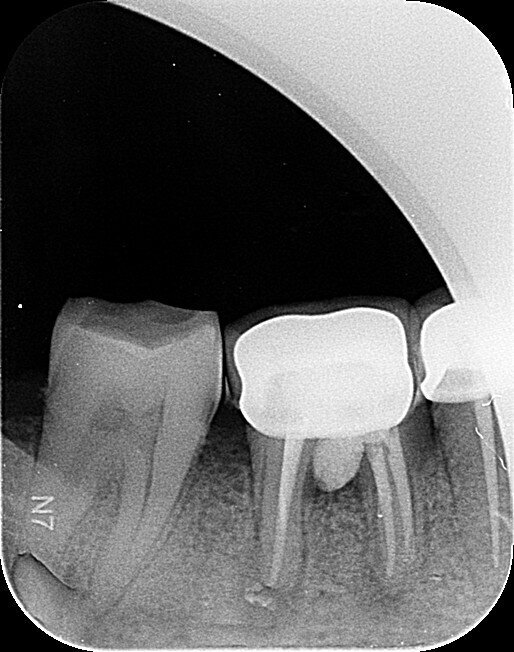

Fig.1a: Pre-op radiograph taken by the referring dentist.

Fig.1b: Pre-op radiograph taken by the author in relation to tooth #46 (January 2019).

When I had a close look at the preoperative radiograph from the referring dentist (Fig. 1a), I observed that there was insufficient obturation of the mesial canals and almost no obturation of the distal canal. Both roots displayed periapical radiolucency. The clinical examination revealed a Grade I mobility, and the tooth was tender to percussion. The periodontal examination ruled out any pockets and loss of attachment. We took an intra-oral periapical radiograph (Fig. 1b), from which we observed the loss of coronal structure and a large radiolucent area over the furcation area and the periapical area of both the mesial and the distal roots. A CBCT scan of tooth #46 was advised to check for any details that may have been missed in the intra-oral periapical radiograph (Figs. 2a–g). From the CBCT scan, it could be observed that there was inadequate obturation of the distal canal on the horizontal plane, no obturation beyond the middle third in the mesial canals and a breach of the floor of the pulp chamber. The questionable prognosis was explainedto the patient, and written consent was obtained.